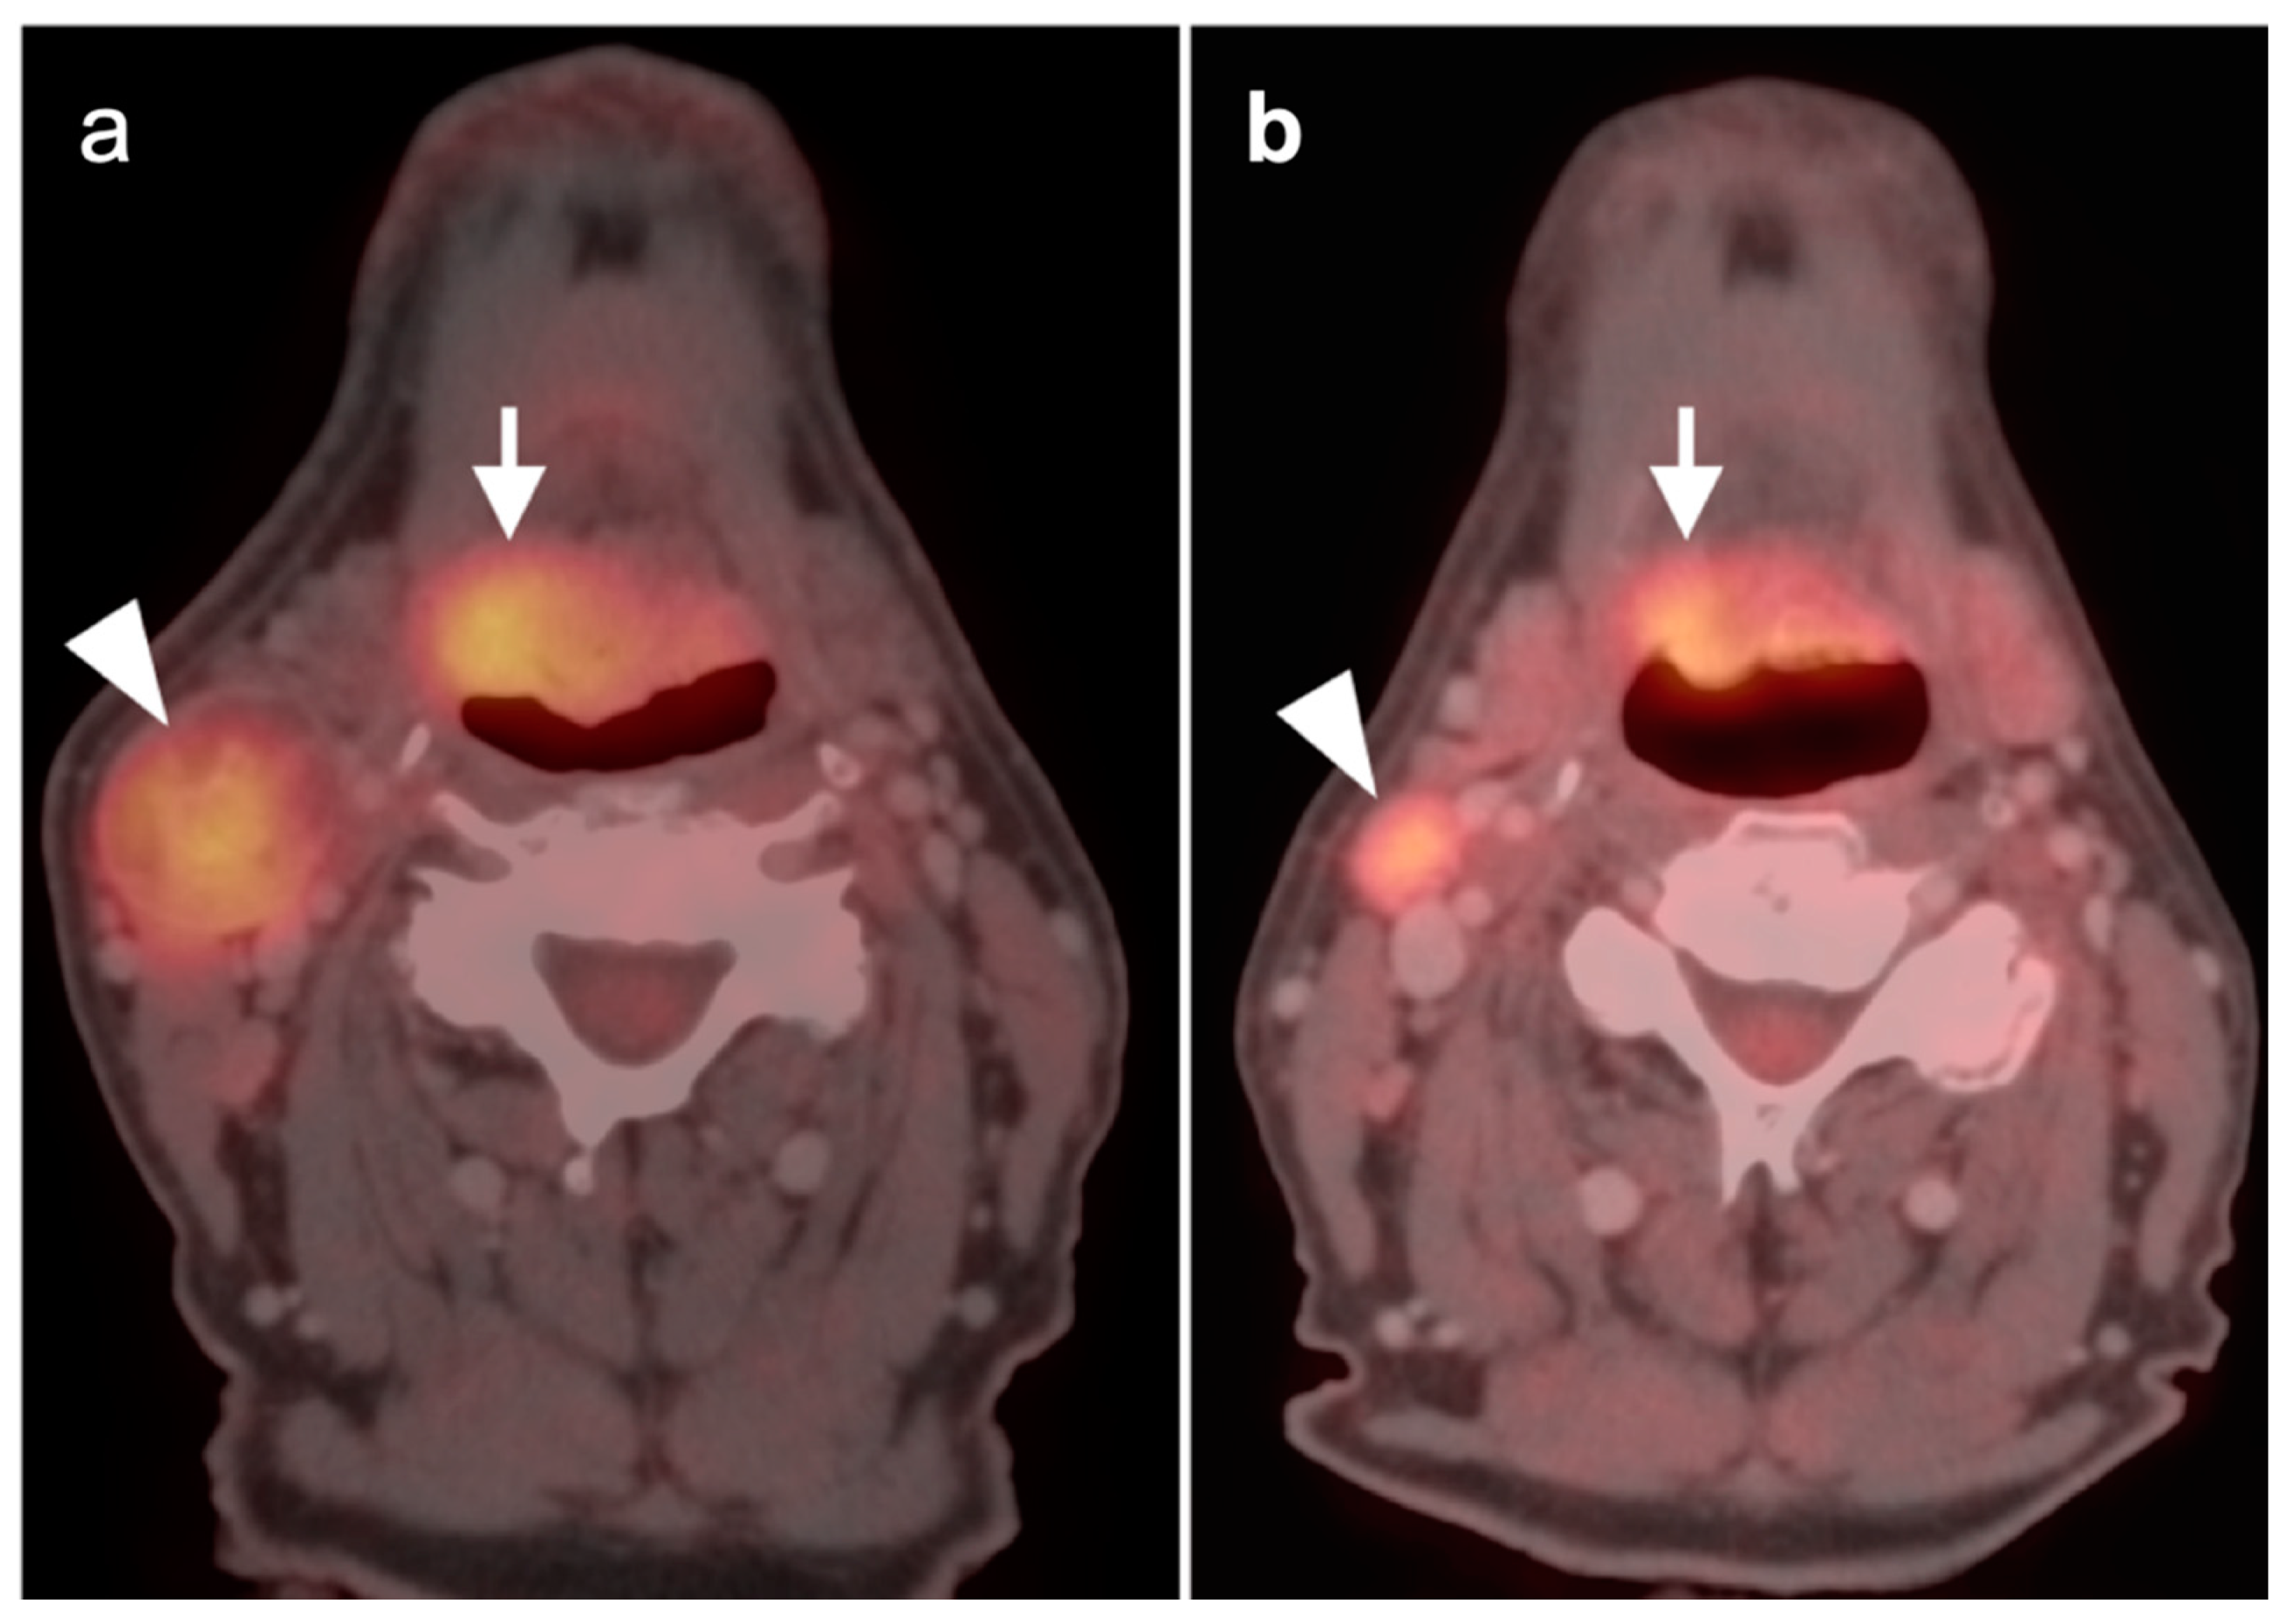

2.2. Squamous Cell Carcinoma of the Head and Neck (SCCHN)

2.5. Major and Minor Salivary Gland, Lacrimal Gland Tumors